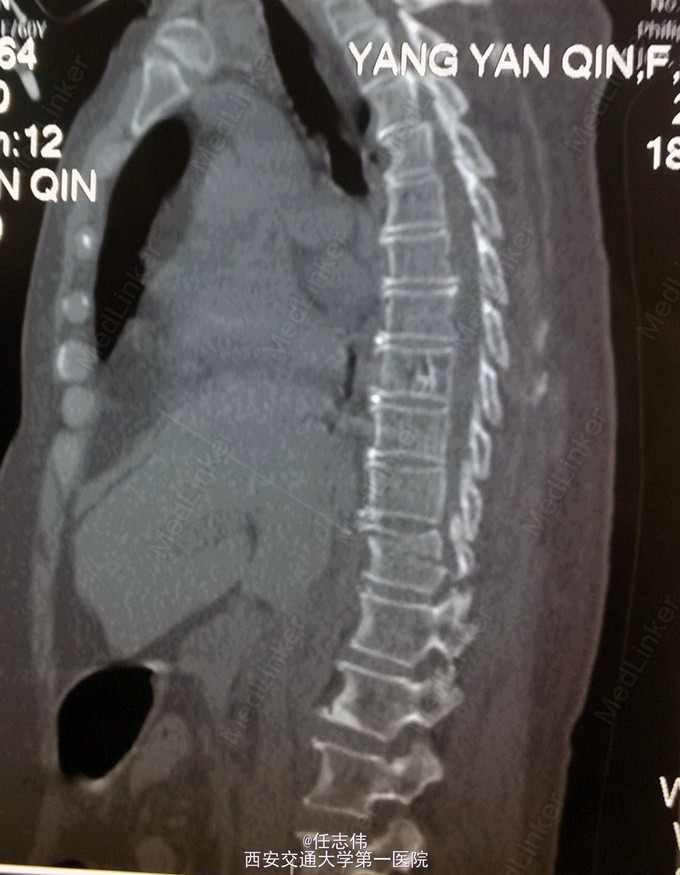

患者女性,60岁,车祸伤致双下肢感觉活动不能8h入院。 8小时前坐农用车时,被横杆撞倒腰部,摔下后感觉胸背部疼痛,双下肢活动不能,伴有短暂昏迷病史。遂来我院就诊。

诊断:1.胸11椎体骨折伴截瘫(Frankel A级)2.闭合性胸部损伤,肺挫伤,多发肋骨骨折,双侧胸腔积液 处理:1.急诊入院告病危,心电血氧监护;2.予以甲强龙冲击治疗;3.次日复查胸部CT,查看肺部损伤情况及胸腔积液,后予以右侧放置闭式引流。患者氧合不稳定,2日后复查胸片胸腔积液减少,予以行后路减压内固定融合术。 手术:术中见局部软组织损伤严重,胸11-12棘上、棘间韧带断裂,胸10、11、12双侧关节突有骨折移位,胸11椎板骨折,胸11左侧不能置入椎弓根螺钉,遂行单纯固定。脊髓局部挫伤明显,并有硬膜破损,予以处理。